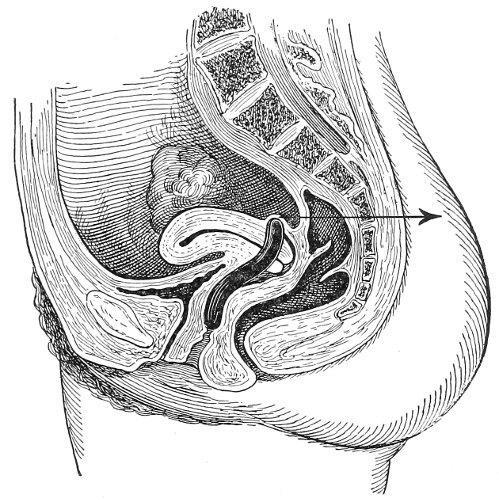

The examination of the uterus and other pelvic structures is often facilitated by dragging the uterus downward with a tenaculum while the vaginal or the bimanual examination is being made. Sensation in the cervix is so slight that little or no pain is experienced in this procedure. The anterior or posterior lip of the cervix is caught with the single or the double tenaculum (Fig. 4), guided along the vaginal finger or introduced through the speculum, and the uterus is drawn down by an assistant in case the bimanual examination is being made, or by the external hand of the examiner in case a simple vaginal examination is made. When this is done the utero-sacral ligaments are made tense, and can be felt like two cords extending from the sides of the cervix outward and backward to the pelvic wall. The posterior surface of the uterus can be palpated often as high up as the fundus. The method is especially useful when the examination is made by the rectum, and in this way the whole posterior surface and the fundus of the uterus may be palpated (Fig. 5).

Fig. 5.—Bimanual examination with one finger in the rectum. The uterus is drawn down with the double tenaculum.

Rectal examination of the pelvic structures is made in a way similar to that already described for the vaginal examination. Bimanual examination may be made by palpating the various organs between the rectal finger and the abdominal hand.